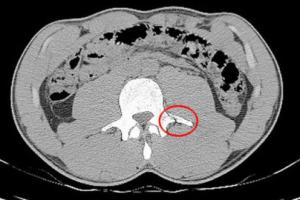

Neymar có một vết gãy xương rất lớn ở phần lưngTờ Sport của Tây Ban Nha đã công bố ảnh scan chấn thương của Neymar dính phải tại World Cup 2014 vừa qua. Ở đây ta nhìn thấy rõ ràng có một vết gãy ở xương rất lớn ở phần lưng dưới tiền đạo Barca. 24/07/2014